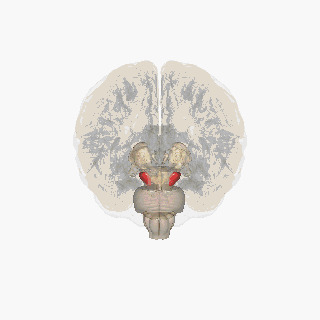

|  Substantia nigra highlighted in red. | |

The substantia nigra (SN) is a basal ganglia structure located in the midbrain that plays an important role in reward and movement. Substantia nigra is Latin for "black substance", reflecting the fact that parts of the substantia nigra appear darker than neighboring areas due to high levels of neuromelanin in dopaminergic neurons.[1] Parkinson's disease is characterized by the loss of dopaminergic neurons in the substantia nigra pars compacta.[2]

The substantia nigra, along with four other nuclei, is part of the basal ganglia. It is the largest nucleus in the midbrain, lying dorsal to the cerebral peduncles. Humans have two substantiae nigrae, one on each side of the midline.